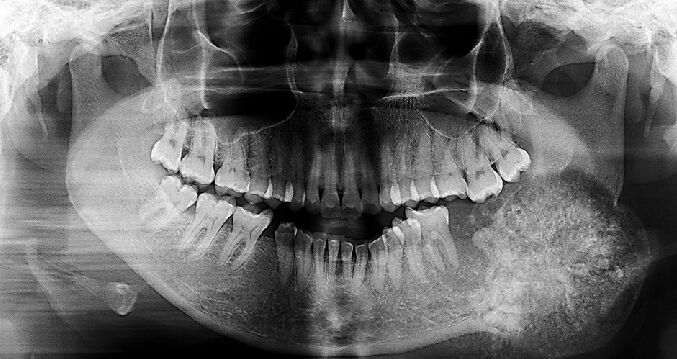

66.17歲男孩因上顎右側有一個無疼痛的腫脹而來求診,經X光檢查(如附圖)發現一個放射線不透過性影像如 箭頭所示之區域,根尖片可見到此病變與周圍界線不清楚,此病患最可能罹患下列何種疾病?

(A)家族性巨大畸形牙骨質瘤(familial gigantiform cementoma)

(B)繁盛性牙骨質骨發育不良(florid cemento-osseous dysplasia)

(C)纖維性發育不良(fibrous dysplasia)

(D)骨化纖維瘤(ossifying fibroma)

B)通常雙側、多處發生,可能會吃穿mucosa露出cemento-like的物質,PANO 初期看起來有點像periapical cyst後期RL的病灶中會包著RO(跟periapical cemento-osseous dysplasia一樣),不會造成bony expansion

D)好發於中年女性下顎後牙區,界限明確,中間出現鈣化組織(unilocular mixed RO/RL),可能會造成bony expansion